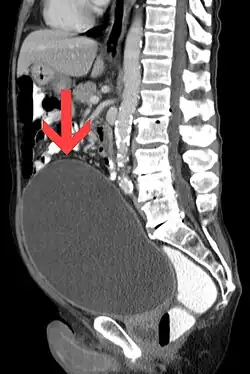

| CT scan in the sagittal plane which reveals a greatly enlarged urinary bladder caused by urinary retention, a condition which often leads to overflow incontinence. | |

Overflow incontinence is a concept of urinary incontinence, characterized by the involuntary release of urine from an overfull urinary bladder, often in the absence of any urge to urinate. This condition occurs in people who have a blockage of the bladder outlet (benign prostatic hyperplasia, prostate cancer, or narrowing of the urethra), or when the muscle that expels urine from the bladder is too weak to empty the bladder normally. Overflow incontinence may also be a side effect of certain medications.